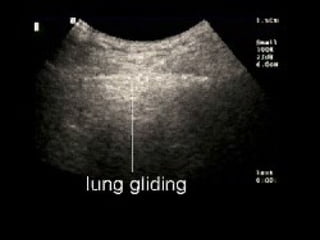

Left panel: Pleural line and A line (real-time).

The pleural line is located 0.5 cm below the rib line in the adult.

Its visible length between two ribs in the longitudinal scan is

approximately 2 cm. The upper rib, pleural line, and lower rib (vertical

arrows) outline a characteristic pattern called the bat sign.

A lines = default normal

Normal lung surface Leftpanel: Pleural line and A line (real-time). The pleural line is located 0.5 cm below the rib line in the adult. Its visible length between two ribs in the longitudinal scan is approximately 2 cm. The upper rib, pleural line, and lower rib (vertical arrows) outline a characteristic pattern called the bat sign.

A lines =default normal  Horizontal echo reflection at exact multiples of intervals from surface to bright reflector.  Dry lung OR PNTX  Decay with depth  Obliterated by B pleura A A A A A A